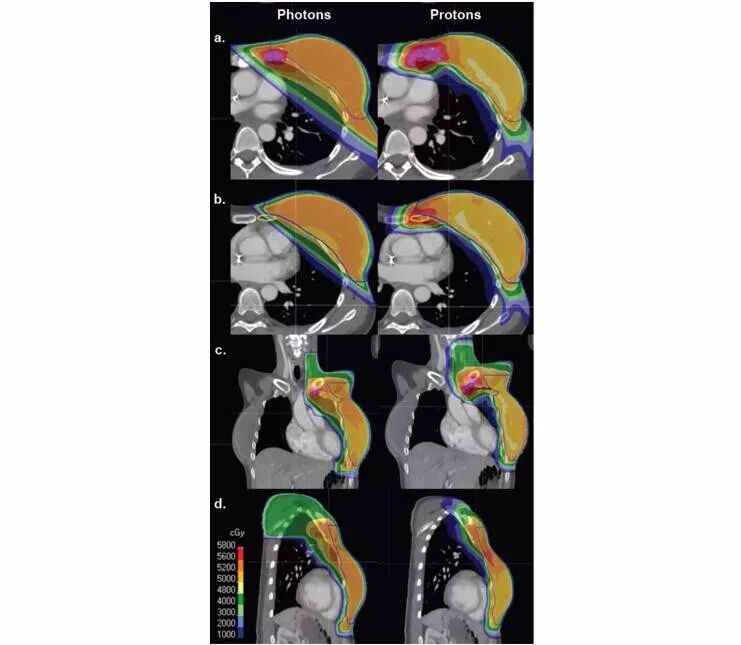

对于传统的光子和电子放疗,在对肿瘤靶区有效照射的同时避免照射心脏和肺部具有挑战性。鉴于质子束在离开靶区后剂量急速下降,质子治疗能够优化肿瘤靶区的剂量,同时减少对周围组织的放射损伤。临床上,减少心脏和肺部的照射剂量可降低迟发心脏和肺部毒性反应的发生率,提高患者的生活质量。

与光子束相比,质子束具有剂量学优势并可保护周围正常组织器官,如对心脏、肺及对侧乳房的照射为中低剂量。因此,既往患有心肺疾病、年轻女性和具有遗传性乳腺癌风险的患者可从质子治疗中获益。对于局部晚期乳腺癌,质子治疗同样具有剂量学优势。例如,质子治疗可避免对心脏亚结构的高剂量照射,并且质子治疗的靶区覆盖率与光子放疗相似或更优。法国诺曼底大学开展的系统性回顾研究表明,质子治疗的靶区覆盖率优于光子放疗甚至光子调强放疗(IMRT, 包括静态或旋转IMRT或螺旋断层放疗)。质子治疗可将平均心脏剂量降低2~3倍;若质子治疗的平均心脏剂量为1 Gy,则传统3D适形放疗(3DCRT)的剂量为3 Gy,IMRT为6 Gy。此外,质子治疗相较于光子放疗可更好地保护肺部并减少乳腺癌患者的平均心脏剂量,能够降低迟发心血管毒性反应的发生风险。

佛罗里达大学研究了质子治疗是否可以提高伴有淋巴结转移风险的乳腺癌患者的治疗比(therapeutic ratio)。研究人员为10例左侧乳腺癌患者分别制定了三维适形光子放疗+质子治疗(3DCX+PT)、3DCRT以及IMRT治疗计划。结果表明,3DCRT的区域淋巴结覆盖率低于IMRT或3DCX+PT。此外,质子治疗不仅提高了区域淋巴结的覆盖率,还降低了心脏、肺和对侧正常组织的照射剂量。

佛罗里达大学于2016年发表在红皮杂志上的II期前瞻性研究(NCT01365845)纳入了18例(左、右侧乳腺癌各9例)需要区域淋巴结放疗的II期或III期浸润性乳腺癌患者。结果表明,质子治疗可显著降低心脏的照射剂量。对于左侧乳腺癌患者,中位平均心脏剂量由传统放疗的5.9 Gy降至质子治疗的0.6 Gy。所有患者中,同侧肺V5和V20显著减少,并且质子治疗可提高IMN和2级腋窝淋巴结的靶区覆盖率。

麻省总医院报告了11例患者的PMRT治疗计划,患者分别接受了质子、部分宽切线光子场(PWTF)和光子/电子场PMRT。PWTF和光子/电子场治疗计划具有理想的靶区体积覆盖率,但质子治疗计划能够更加均匀地覆盖靶区,并且与PWTF和光子/电子治疗计划相比,质子治疗计划能够很好地保护心肺组织。